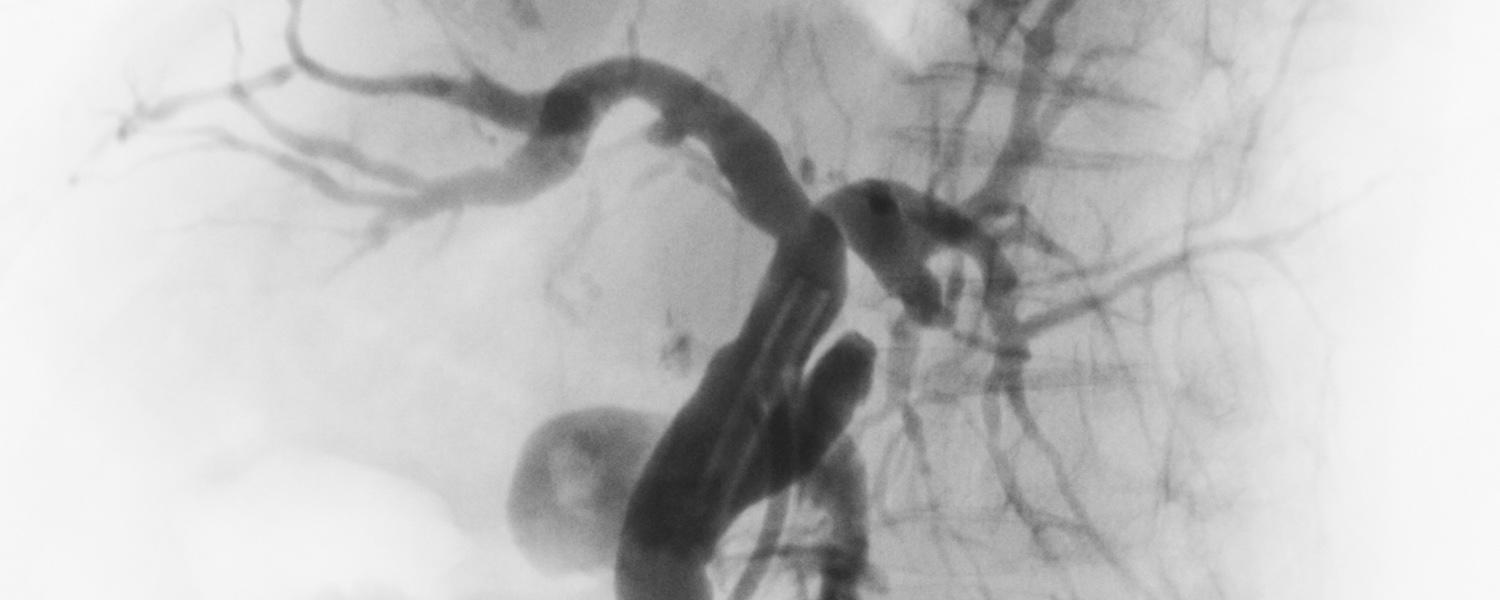

The Interventional Neuroradiology fellowship is a one or two-year program jointly run by the departments of Neurosurgery and Radiology. The program covers all aspects of diagnostic and therapeutic endovascular procedures for vascular pathologies of the brain and spine.

Approximately, 700 patients with neurovascular disease are seen yearly for evaluation and follow-up. Currently over 200 patients are treated annually via minimally invasive endovascular means such as endovascular coiling, therapeutic embolization, and carotid stenting. We are an internationally recognized centre providing state-of-the-art endovascular stroke treatment. As well, surgical volumes and expertise in open neurosurgery have been maintained with the availability of specialized procedures such as aneurysm clipping, carotid endarterectomy, resection of vascular malformations, and extracranial-intracranial artery bypass.